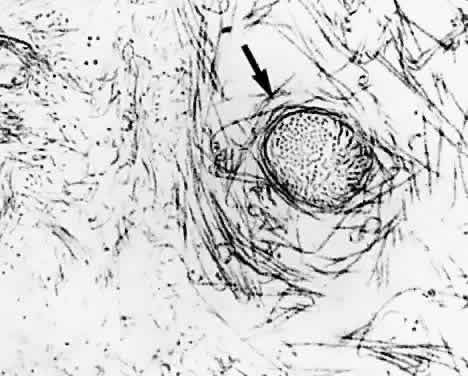

Fig. 11. Vitreous structure in childhood. A: Central vitreous structure in a 6-year-old child has hyalocytes in a dense vitreous cortex. No fibers are seen within the vitreous. B: Vitreous structure in an 8-year-old child shows the ciliary processes (arrow). The vitreous cortex and hyalocytes can be identified. Significant amounts of vitreous extrude through the premacular vitreous cortex into the retrocortical (preretinal) space, yet no fibers are present in the vitreous body.